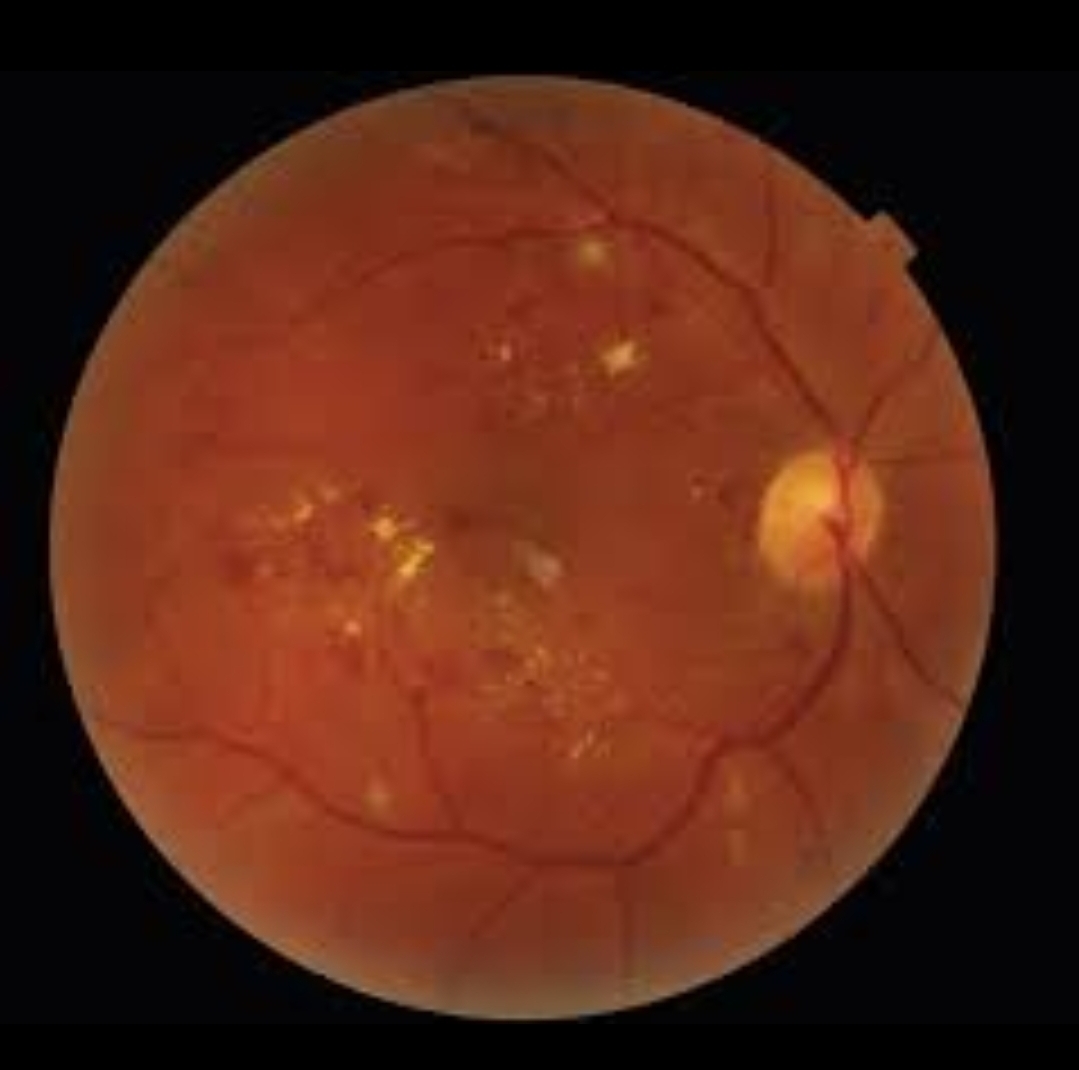

हाई ब्लड प्रेशर के मरीजों में आंखों की रेटिना की नसों में बदलाव दिखाई देता है। अगर समय रहते इसका पता चल जाए, तो मरीज को बड़ी समस्या से बचाया जा सकता है। इसी तरह, डायबिटीज के मरीजों में डायबिटिक रेटिनोपैथी का खतरा होता है, जो आंखों की जांच से शुरुआती स्तर पर पकड़ा जा सकता है।

स्ट्रोक के मामलों में भी आंखों की जांच महत्वपूर्ण भूमिका निभाती है। आंखों की नसों में ब्लॉकेज या थक्के बनने के संकेत स्ट्रोक के खतरे को दर्शा सकते हैं। अगर इसे समय पर पहचान लिया जाए, तो मरीज की जान बचाई जा सकती है।

आजकल आधुनिक तकनीक की मदद से आंखों की जांच और भी आसान और सटीक हो गई है। डिजिटल रेटिना स्कैन, ऑप्टिकल कोहेरेंस टोमोग्राफी (OCT) जैसी तकनीकों के जरिए डॉक्टर बहुत ही बारीकी से आंखों की स्थिति का विश्लेषण कर सकते हैं।